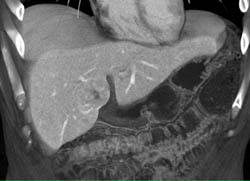

Focal Nodular Hyperplasia (FNH)